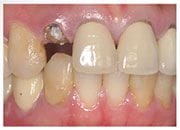

陳小姐是一位美貌與才氣兼具的事業女強人,在一次晚宴中,已經做了十多年的門牙假牙脫落,陳小姐緊急求助黃醫師,立刻進行"立即式植牙" ,將已經蛀壞的牙根拔除,植入人工牙根,再做上美觀的假牙,讓陳小姐無後顧之憂的面對明日的工作。

治療前